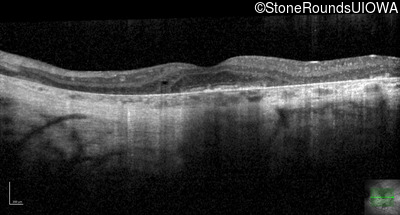

Optical Coherence Tomography - Right - 20/50 sc

Exemplar / OCT Stack